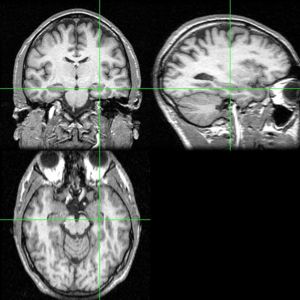

海馬的三維位置大腦海馬是位於腦顳葉內的一個部位的名稱,人有兩個海馬,分別位於左右腦半球。它是組成大腦邊緣系統的一部分,擔當著關於記憶以及空間定位的作用。名字來源於這個部位的彎曲形狀貌似海馬。

海馬, DG: 齒狀回儘管關於海馬與其向鄰近的大腦皮層的表述尚缺乏一致的觀點,通常情況下術語上的“海馬結構”指的是齒狀回,CA1-CA3部位(或CA4,常稱為hilus區並被認為是齒狀回的一部分),以及腦下腳(另見阿蒙神之角)。 CA1與 CA3 部位構成嚴格意義上的海馬。